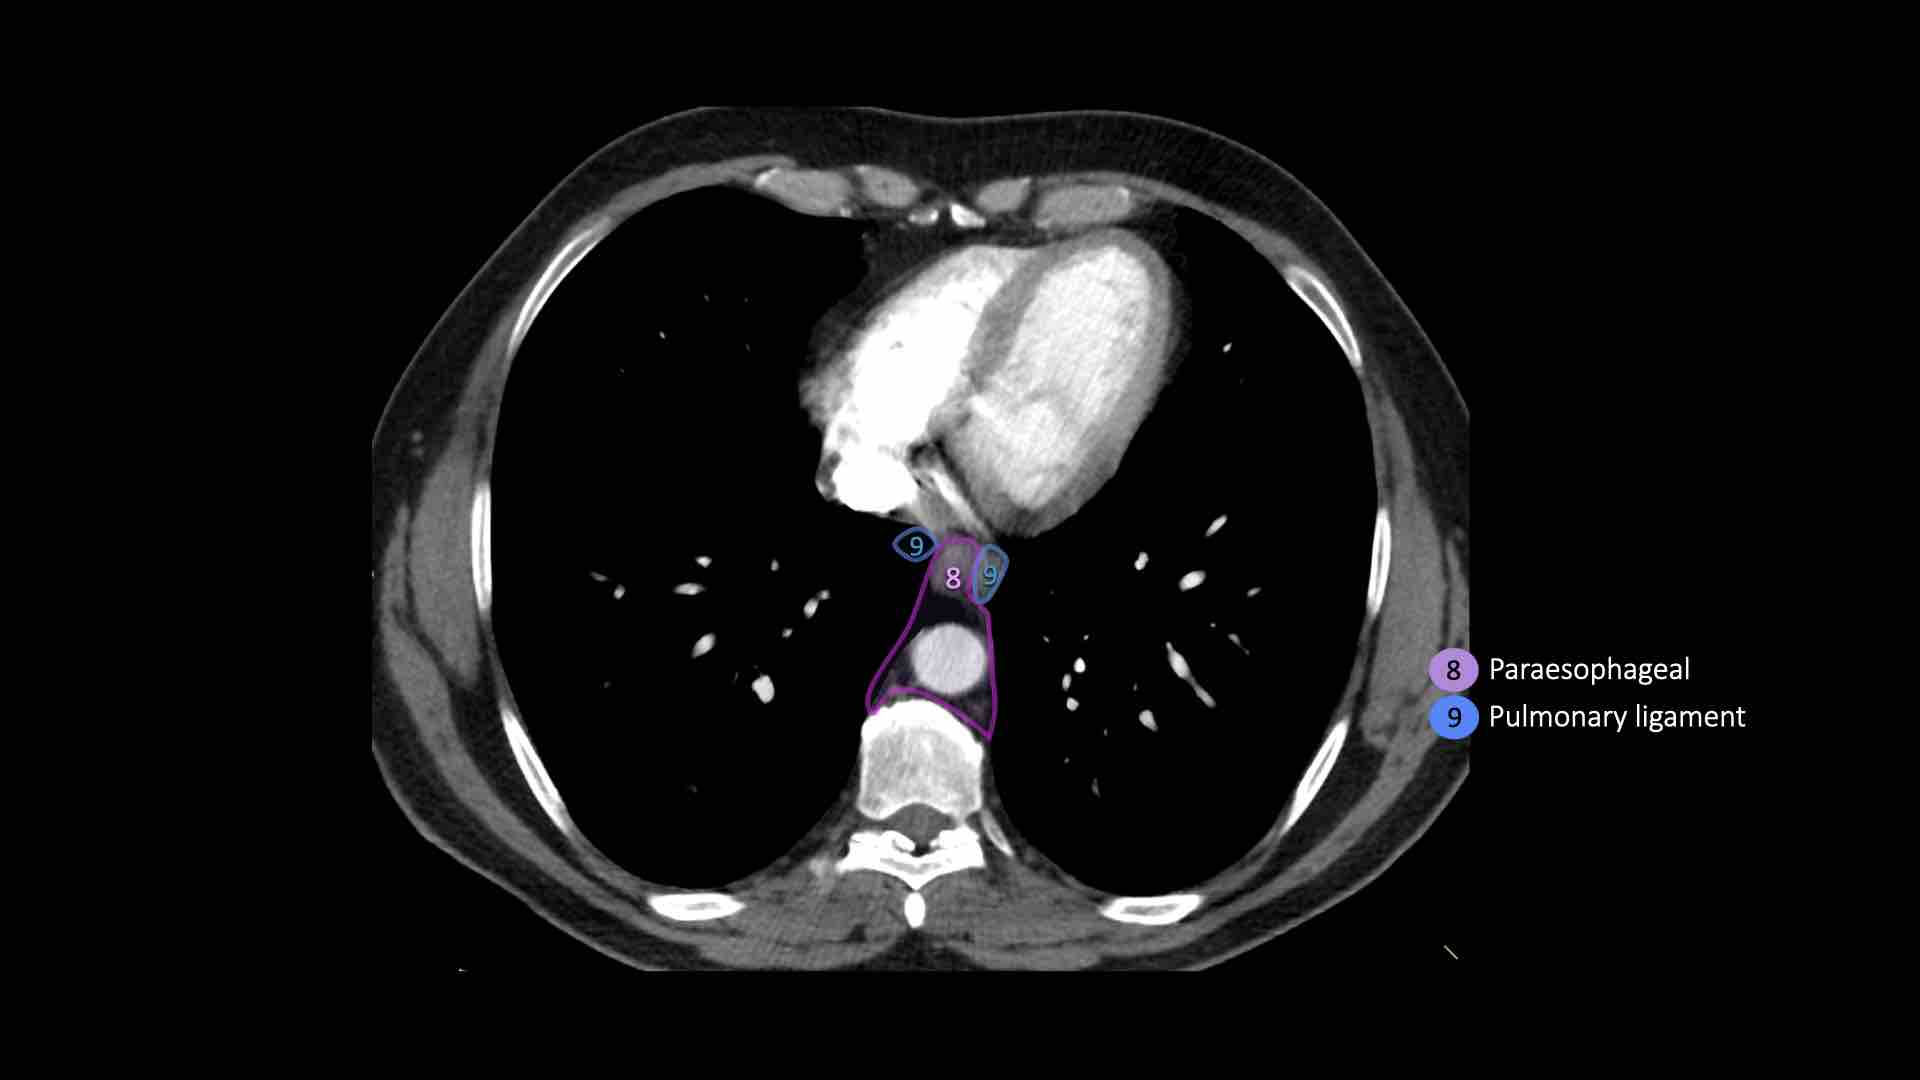

8. Cạnh thực quản

Các hạch nằm dưới carina.

9. Dây chằng phổi

Các hạch nằm trong dây chằng phổi.

8. Hạch cạnh thực quản

Các hạch này nằm bên dưới các hạch dưới carina và trải dài xuống đến cơ hoành.

Bên trái là hình ảnh dưới mức carina.

Bên phải thực quản là một hạch nhóm 8.

9. Hạch dây chằng phổi

Hạch dây chằng phổi nằm trong dây chằng phổi, bao gồm các hạch ở thành sau và phần dưới của tĩnh mạch phổi dưới.

Dây chằng phổi là phần kéo dài xuống dưới của các nếp gấp màng phổi trung thất bao quanh rốn phổi.